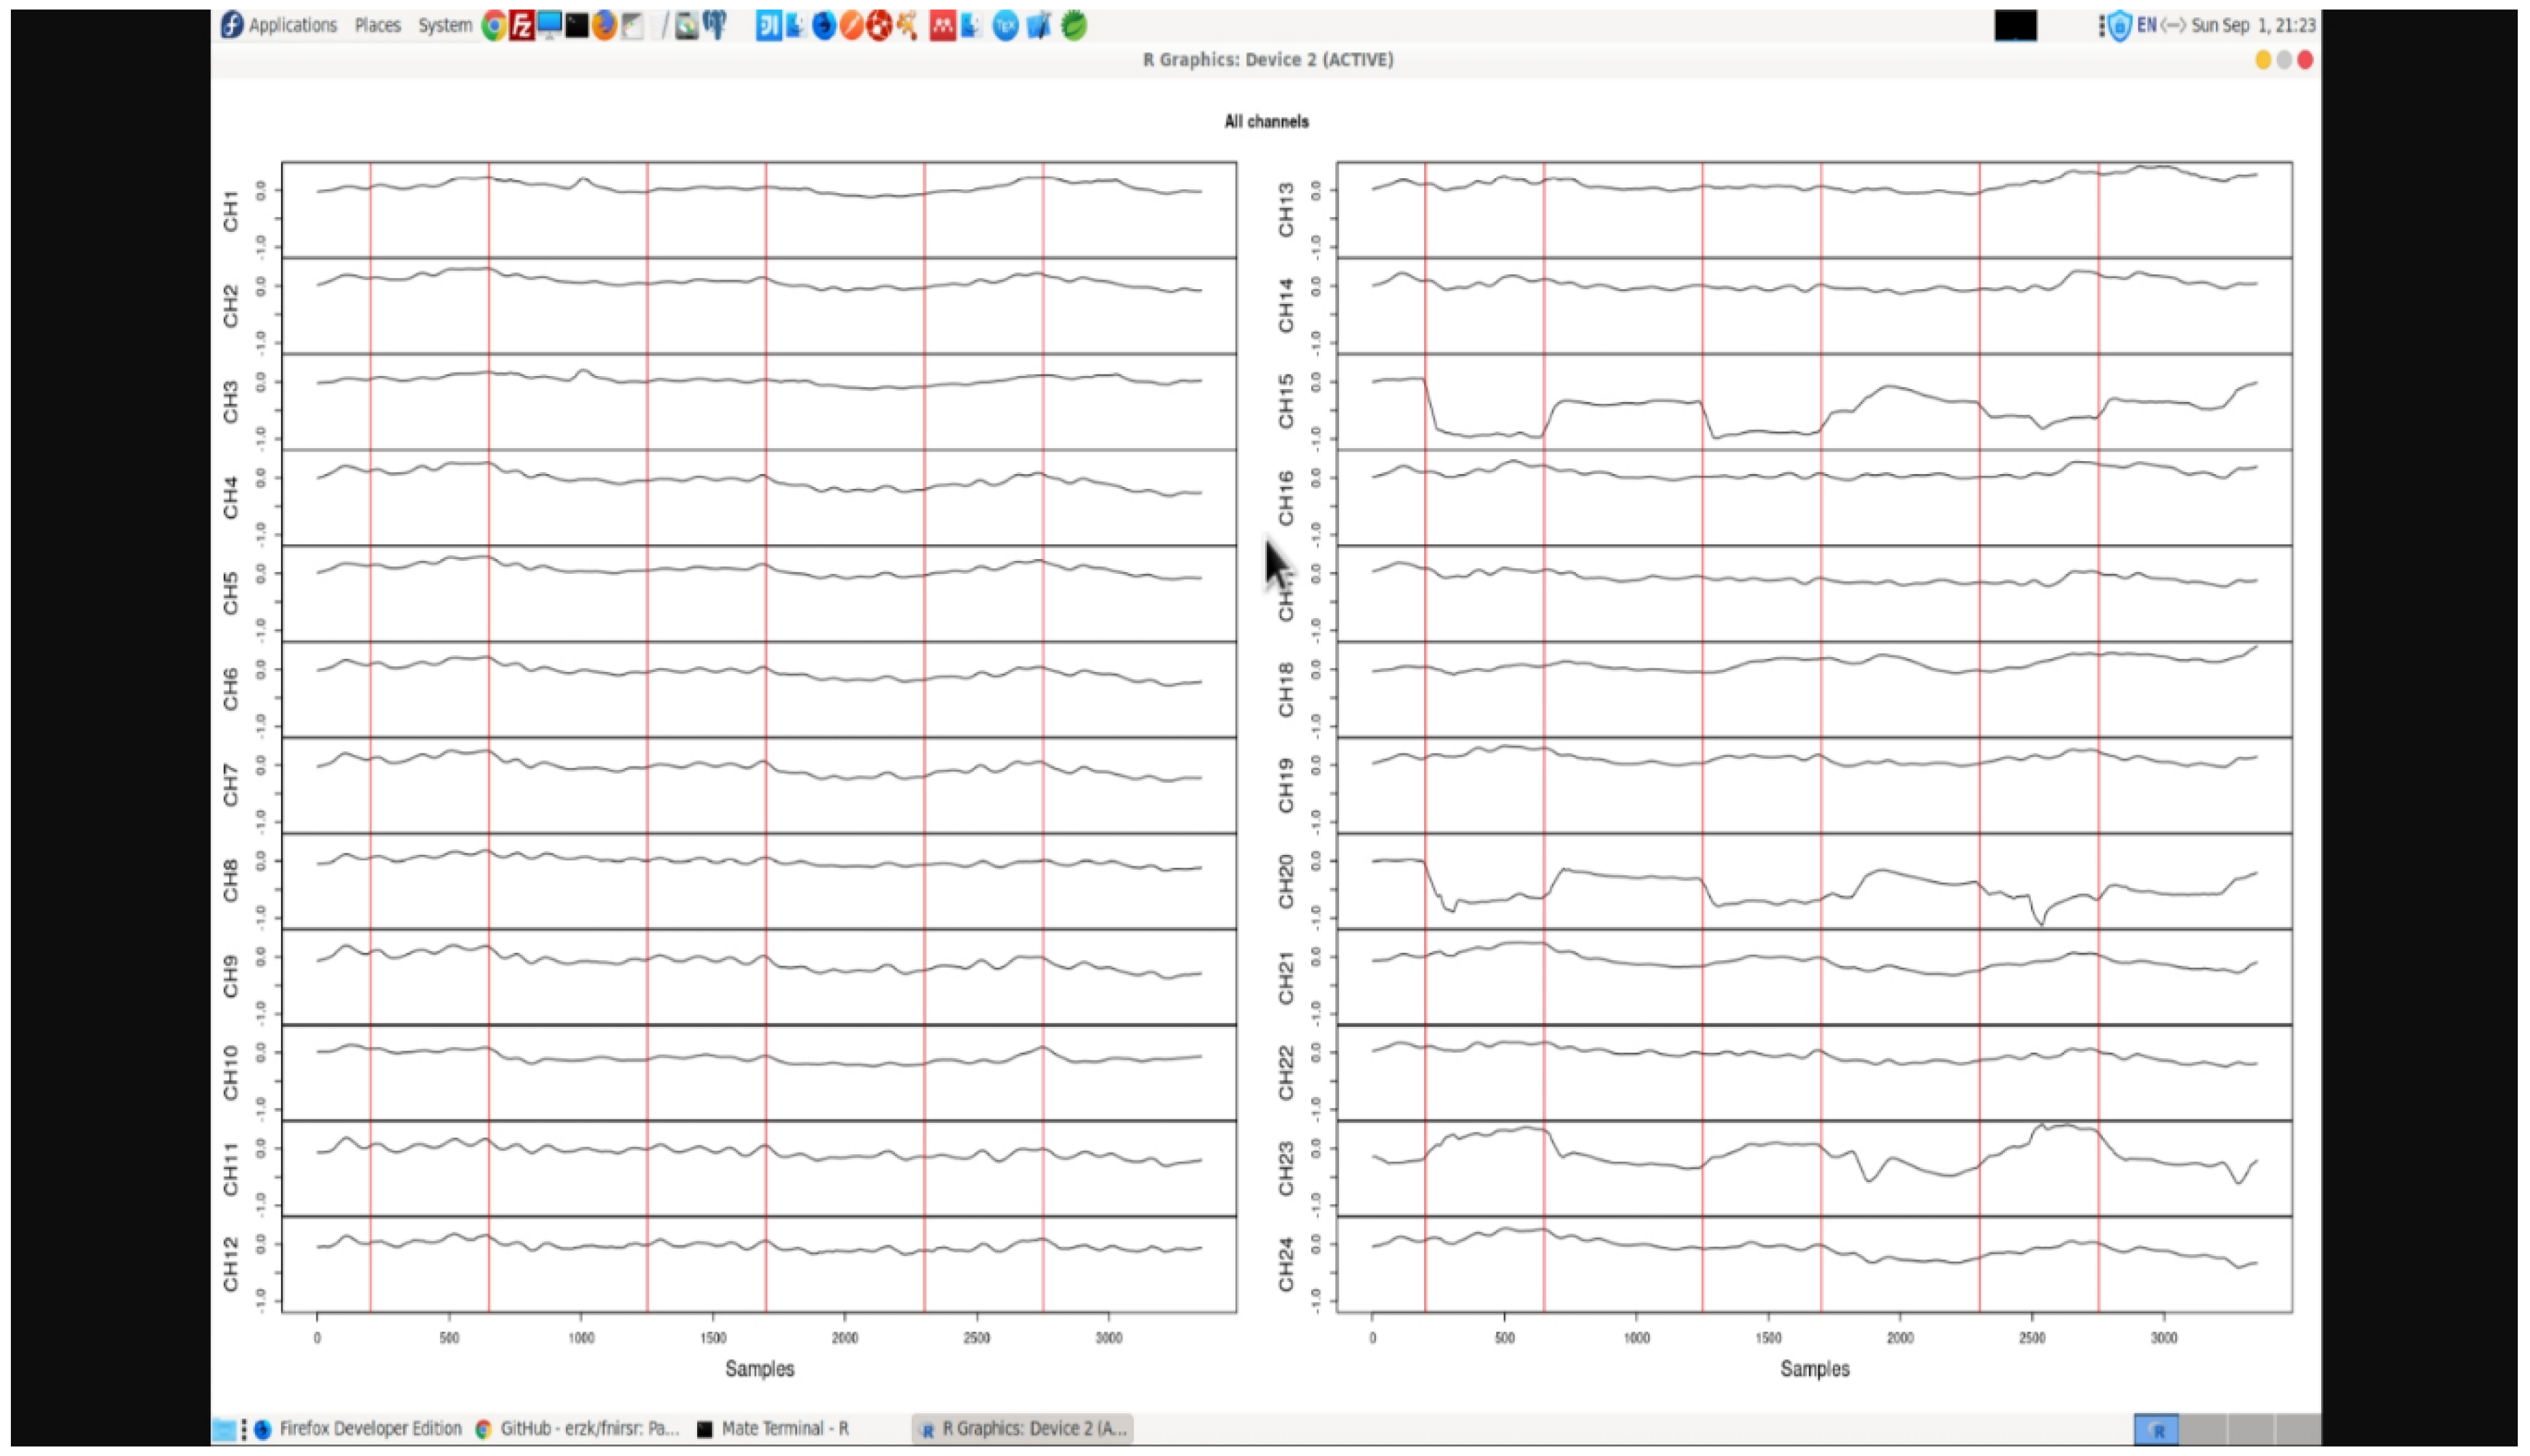

Data Acquisition Approaches and Limitations with a Standalone Setup